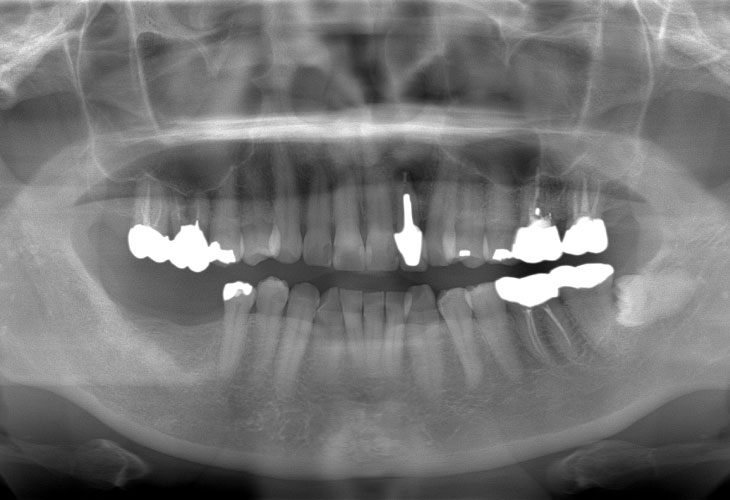

BEFORE

右下奥歯の歯が無い。インプラント治療をしたい。

右下臼歯部欠損

インプラント(右下6・7)

インプラント: 4ヶ月/6回

オールセラミック、E-MAX CAD: 4ヶ月/6回

インプラント: 700,000円

オールセラミック、E-MAX CAD: 269,500円

合計 969,500円